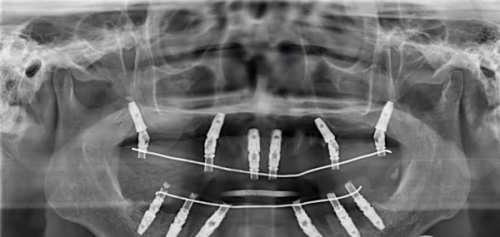

3D数字化导板:通过CBCT扫描和口内3D建模,能把误差控制在0.1mm内。单颗种植仅需10分钟,还能避开血管神经。

技术适用人群:单颗/多颗牙缺失,推荐使用3D导板种植。半口/全口牙缺失,适合即刻负重技术,当天就能修复咀嚼功能。骨量不足患者,可做数字化导板种植,无需植骨。